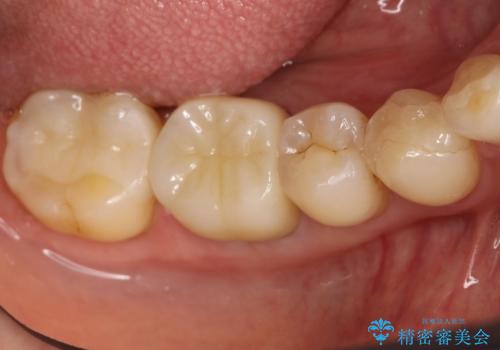

[深い虫歯] 根管治療・歯周外科治療を行い歯を保存する

![[深い虫歯] 根管治療・歯周外科治療を行い歯を保存するの症例 治療後](https://seimitsushinbi.jp/wp/wp-content/uploads/2019/10/f94f918301554464d21b1fb7c0a3d93b-500x350.jpg?v=1572444693)